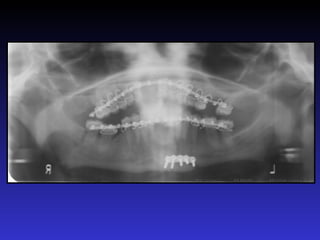

Lỗi khi chụp

Đeo hàm giả cản quang trong miệng khi chụp phim.